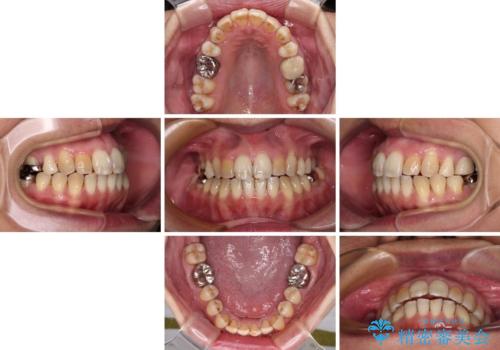

前歯の後戻り インビザラインでの再矯正治療

舌のトレーニングをしっかりと行ってくださり、10ヶ月で希望通りの歯列となりました。

日頃から飲まれる飲み物の影響で着色しやすいため、来院の度に着色除去のクリーニングも行っていました。